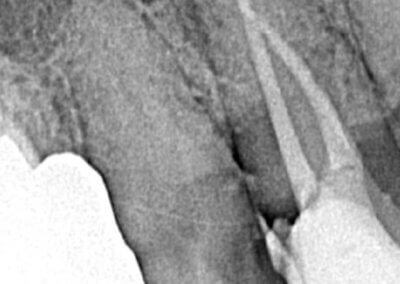

Endodonția este o ramură esențială a stomatologiei, axată pe diagnosticarea, prevenirea și tratamentul afecțiunilor pulpei dentare și a țesuturilor periapicale. Această specialitate joacă un rol crucial în salvarea dinților naturali, evitând extracțiile și menținând sănătatea orală pe termen lung. Prin tehnici avansate și echipamente de ultimă generație, endodonția asigură tratamente precise și eficiente, contribuind la redarea sănătății și funcționalității dinților într-un mod durabil și predictibil.

Utilizarea tehnicilor moderne asigură un tratament rapid, precis și confortabil pentru pacient.